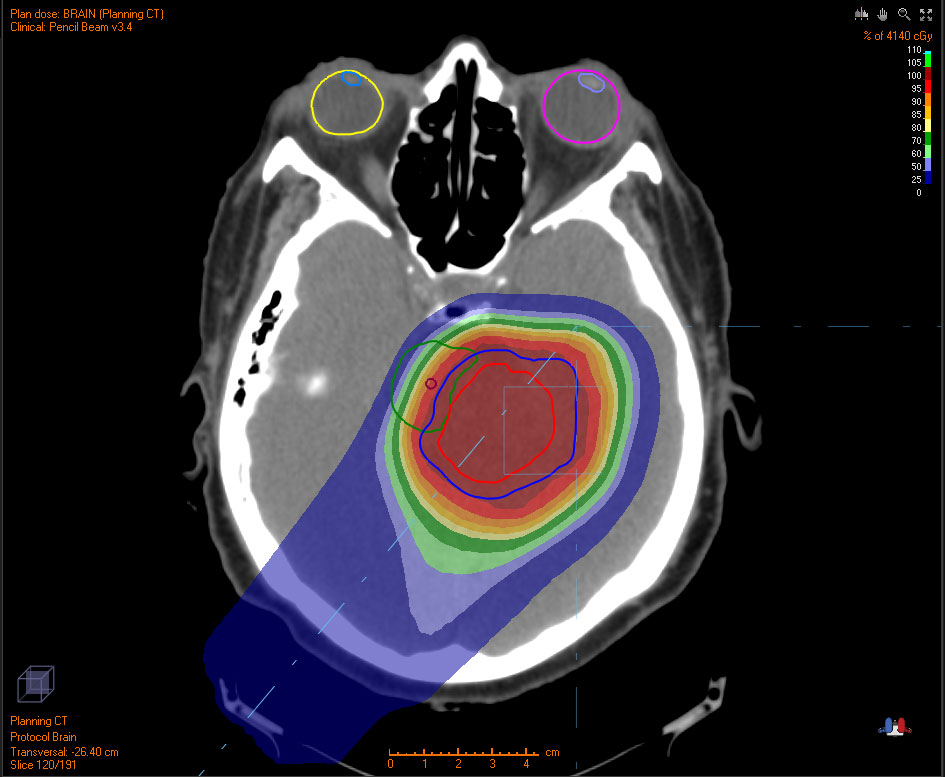

Below are examples of tumors treated with proton therapy and standard X-rays. In both cases, the tumor is treated with radiation. However, proton therapy delivers most of the radiation directly to the tumor, leaving much of the surrounding tissue unaffected. In contrast, standard X-ray radiation exposes a larger area of healthy tissue to radiation.

WITH X-RAYS

Colored area indicate radiation exposure.